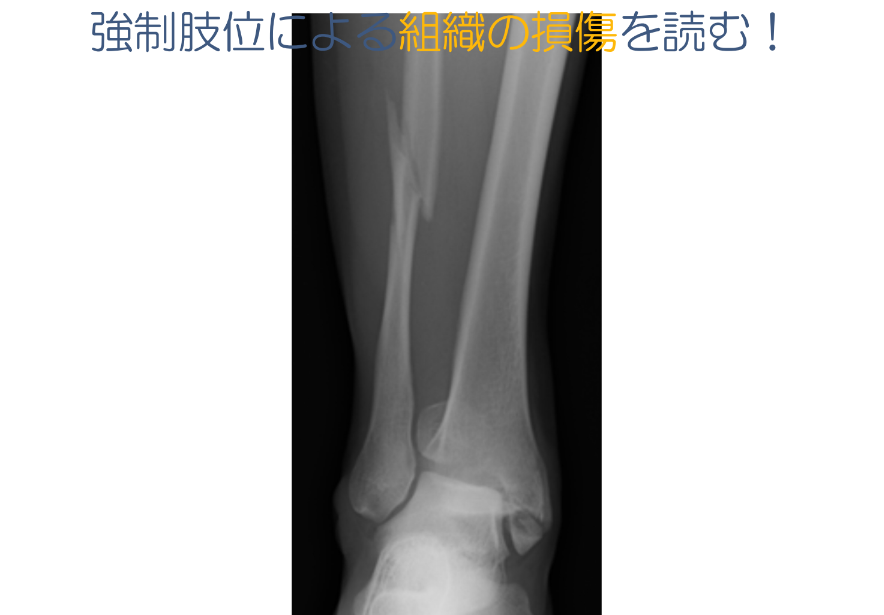

・組織の損傷を読む

・遠位脛腓靭帯損傷